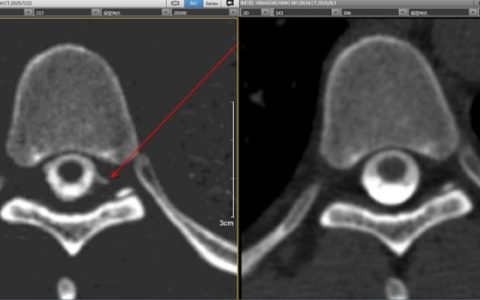

胡永红主任和陈晨医师按照第九版新冠病毒防控要求身着二级防护服全程接诊患者,紧急完善新冠肺炎抗原检测及核酸快检、普检,评估病情及查看资料,该患者现妊娠41+5周,因巨大儿需立即行剖宫产结束妊娠。在等待检验结果的同时,紧急联系手术室高运泽主任准备负压层流手术室做好手术准备,全程在胡永红主任指挥下一切如演练时有条不紊的进行着。

焦急等待中患者的核酸抗原及核酸检测结果出来了,是阴性!胡永红主任把提起的心稍稍放松了一下,但因此次新冠肺炎病毒感染性、隐匿性强,不能完全排除该患者是否为新冠病毒携带者,仍需注重防护,这关系着整个妇产科患者甚至全院患者及医务人员的生命健康安全!胡主任深知防守不能有丝毫松懈,让病毒有可趁之机。一切手术准备就绪,手术室护士长胡蝶身着二级防护从特殊通道接患者入负压层流手术室,苏林梅副主任、曾秋媚医师及麻醉科医师在身着二级防护下顺利地实施了子宫下段剖宫产术,新生儿体重4000克,母子平安!